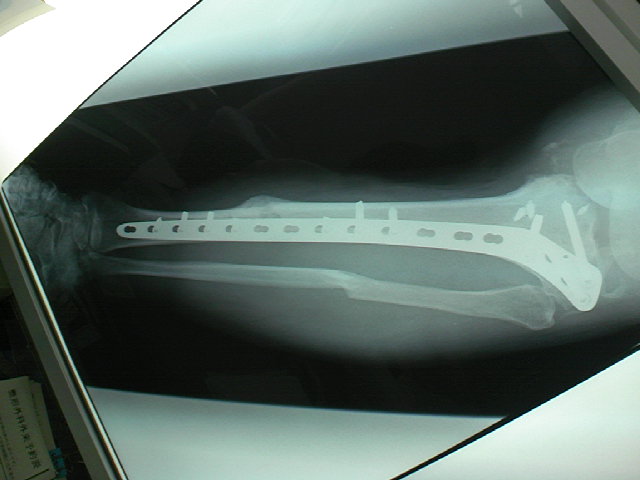

昨日は病院で整形の外来診察。記念撮影も兼ねて・・・(あ~レントゲンです)

ボッキリと折れた骨も引っ付いたようで、一安心。膝はまだまだ弱いですが・・・

しっかしプレートとボルトが生々しい